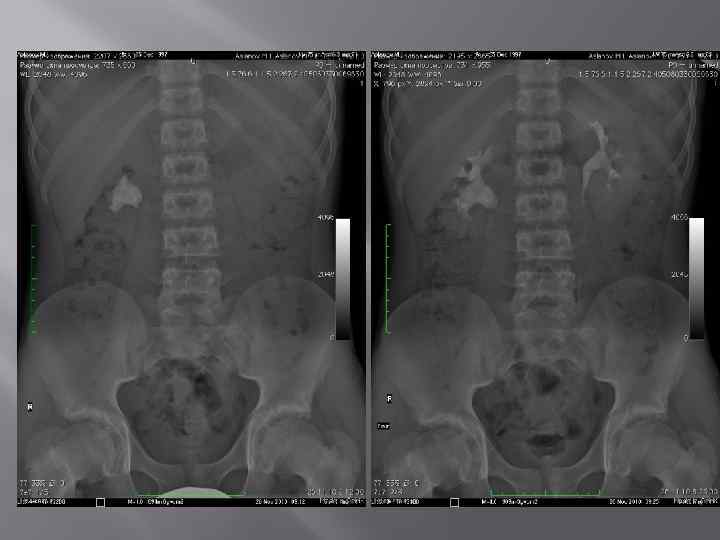

Мочекаменная болезнь

Мочекаменная болезнь ХРОНИЧЕСКИ ПРОТЕКАЮЩЕЕ ЗАБОЛЕВАНИЕ ХАРАКТЕРИЗУЮЩЕЕСЯ НАЛИЧИЕМ В ПОЛОСТНОЙ СИСТЕМЕ ИЛИ ПАРЕНХИМЕ КАМНЕЙ, ФОРМИРУЮЩИХСЯ ИЗ СОСТАВНЫХ ЧАСТЕЙ МОЧИ. Составляют 30 -40% всех хирургических заболеваний. Различают одиночный камень, множественные лоханочные и комбинации лоханочного камня с чашечковым или поренхиматозными. Выделяют понятие рентгенонегативного камня, т. е. камень который не даёт тени на рентгенограмме.

Экскреторная урография -рентгненегативные камни- дефект наполнения - Рентгенпозитивные камни-тень камня усиливается

Уролитиаз Камни чашечек

Коралловидные камни